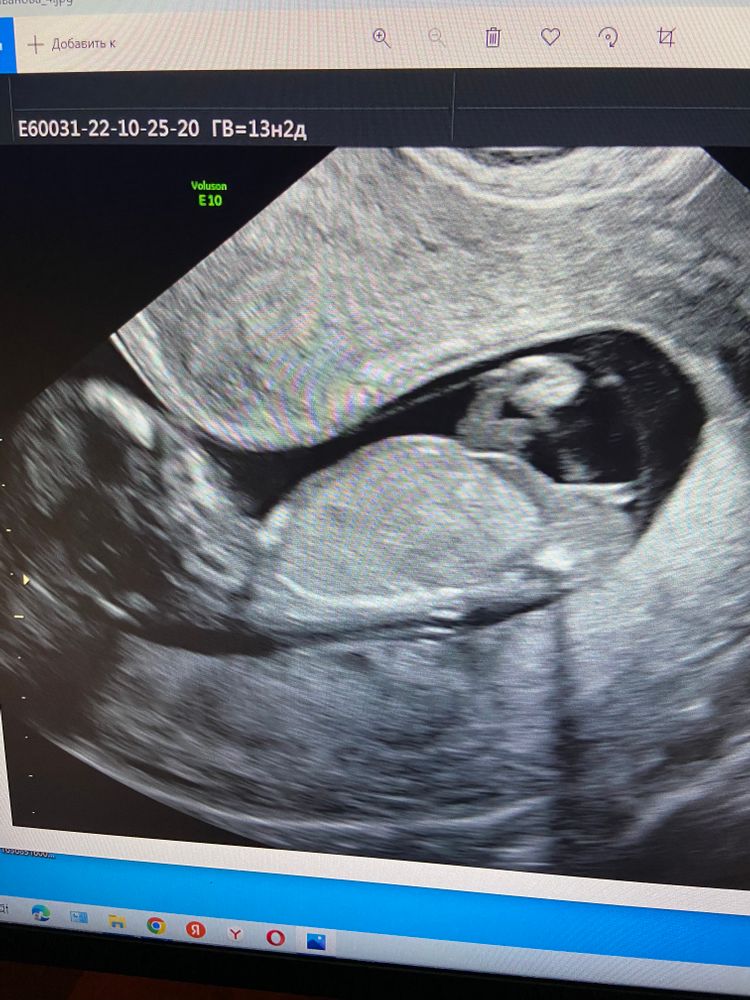

Ждем 2 скрининг

Мария //рожу дочку в 2021//, почти все высказались за девочку, почему же врач предположил мальчика 🤔

Похоже на девочку.

Я думаю, что это девочка)

Мне кажется девочка

Мальчик

Девочка у вас

Так это ещё половой бугорок. Мне кажется у вас девочка.

Одной мне кажется что мальчик?

Ирина Матвеева скоро стану мамой , нет, не одной, врачу-узи тоже